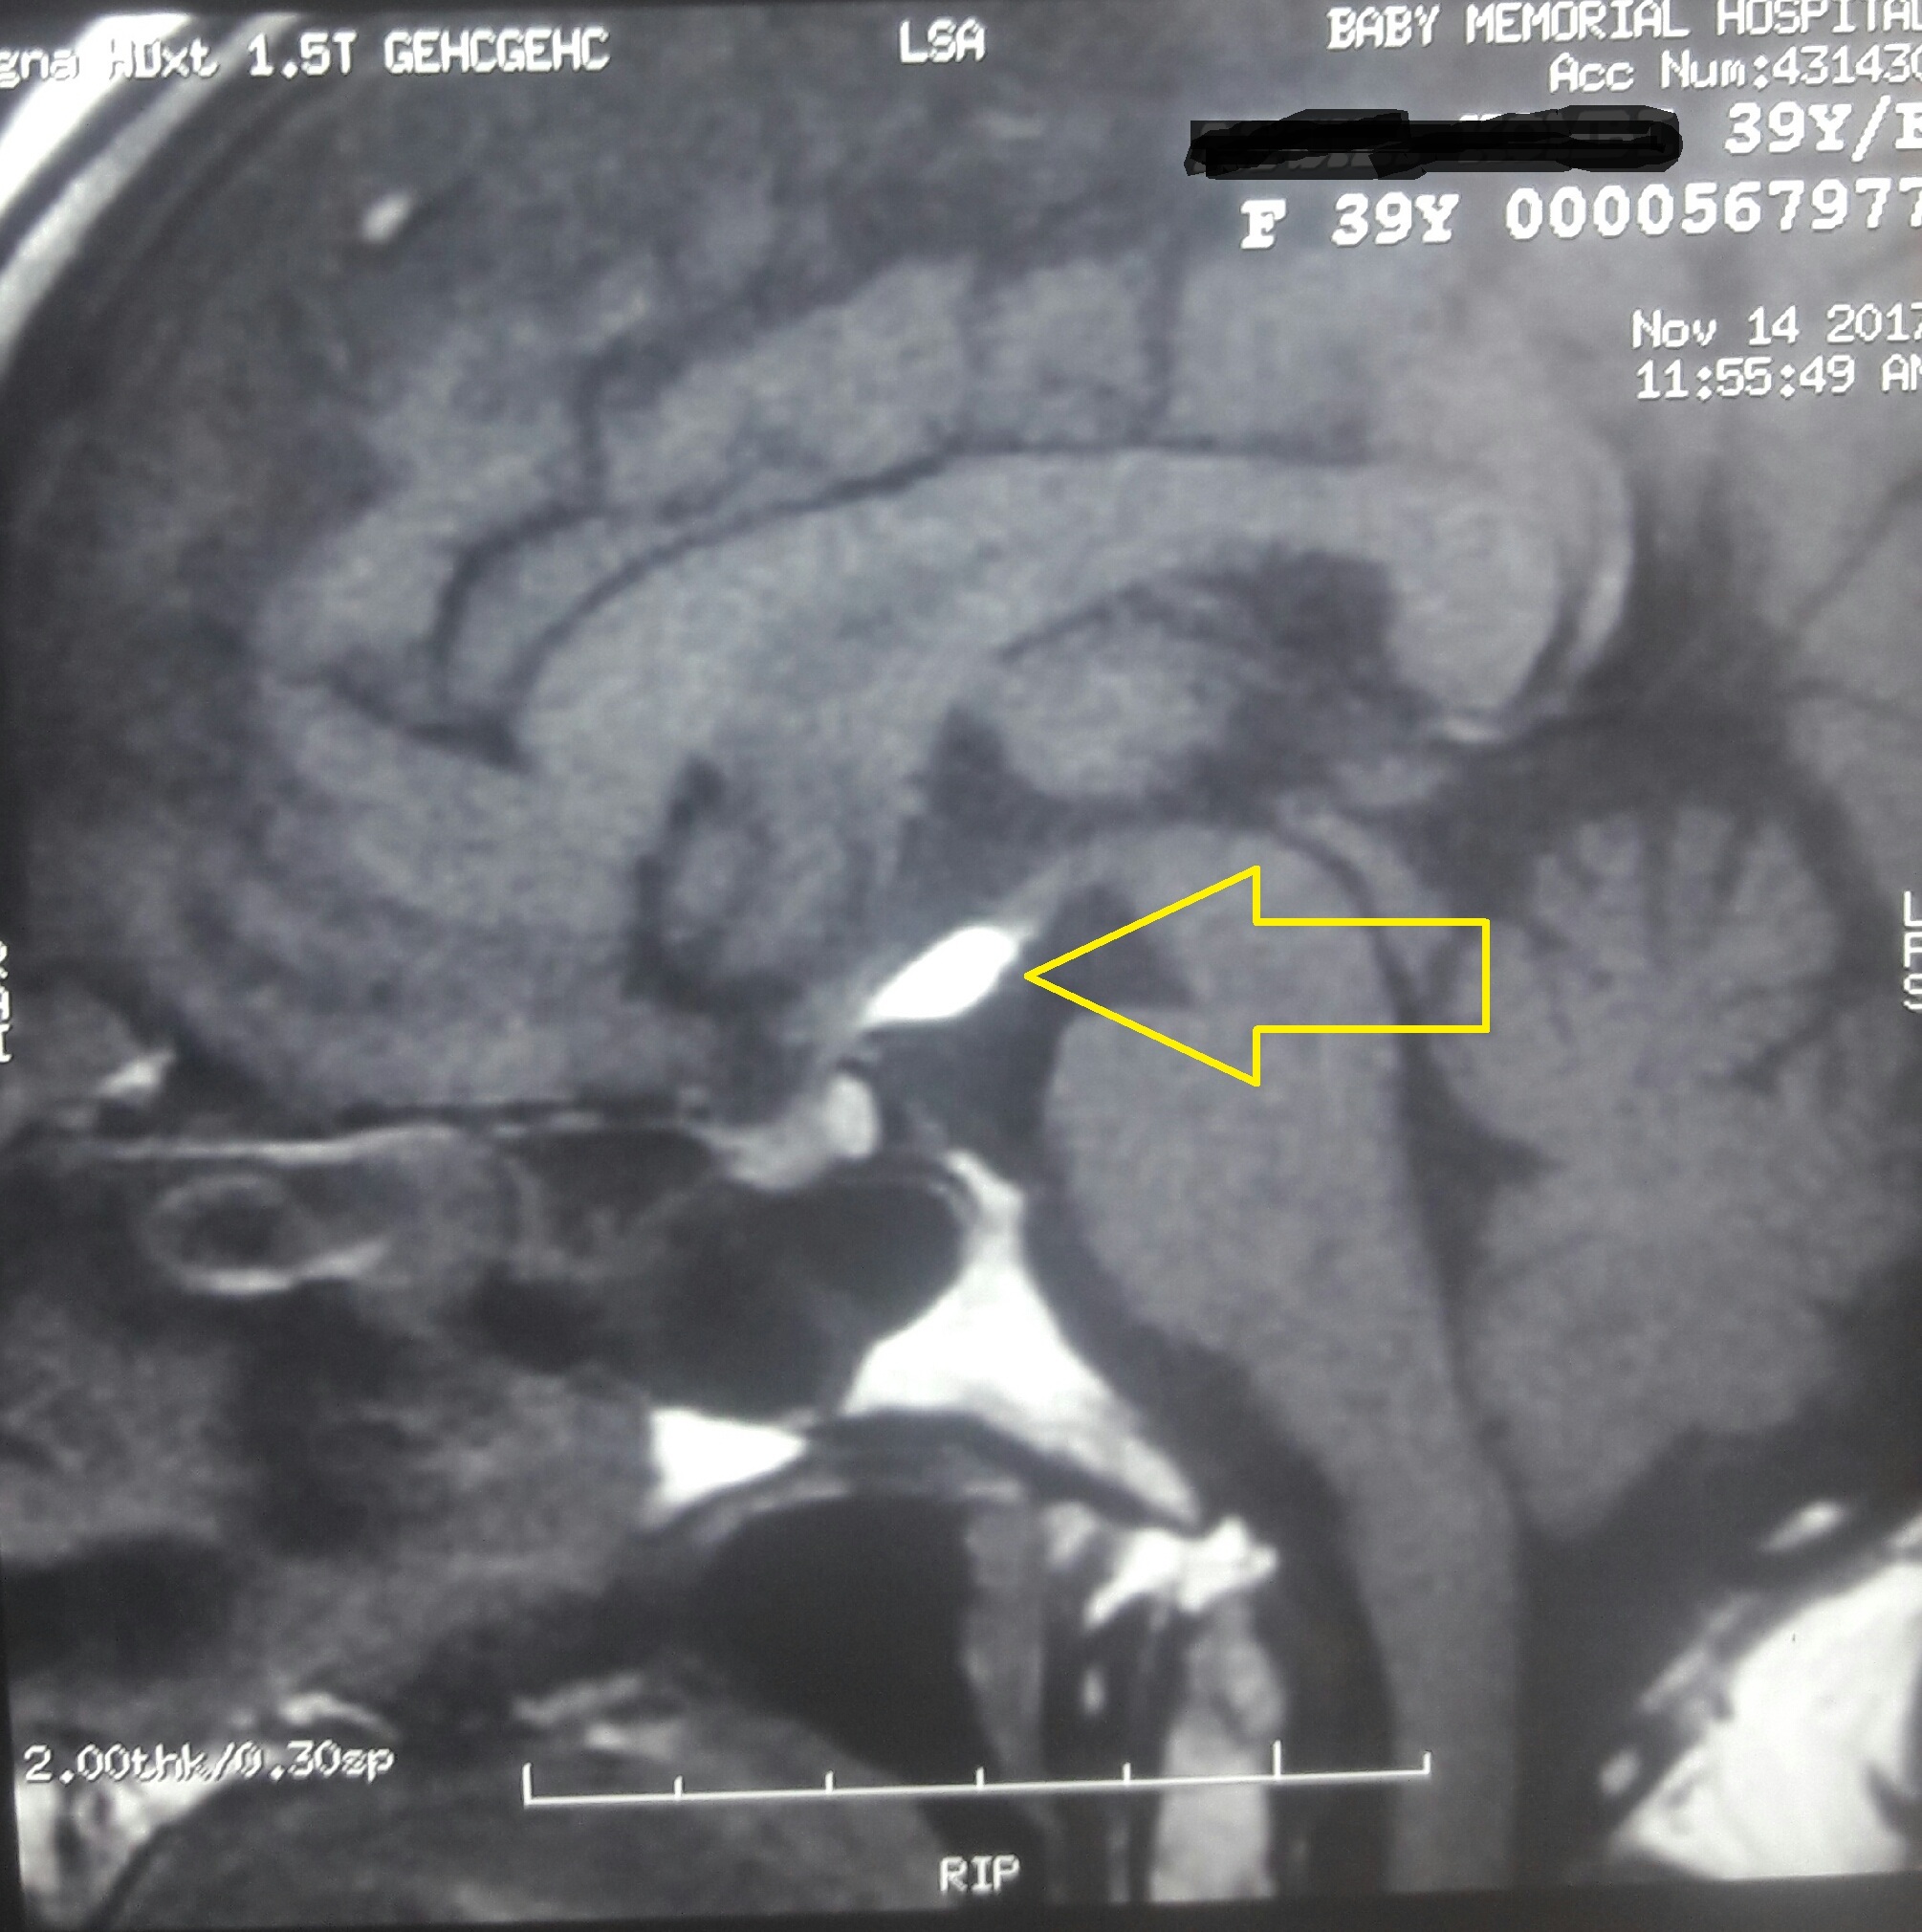

Tuber cinereum lipoma

Intracranial lipomas, Tuber cinereum, Intracranial tumoursAbstract